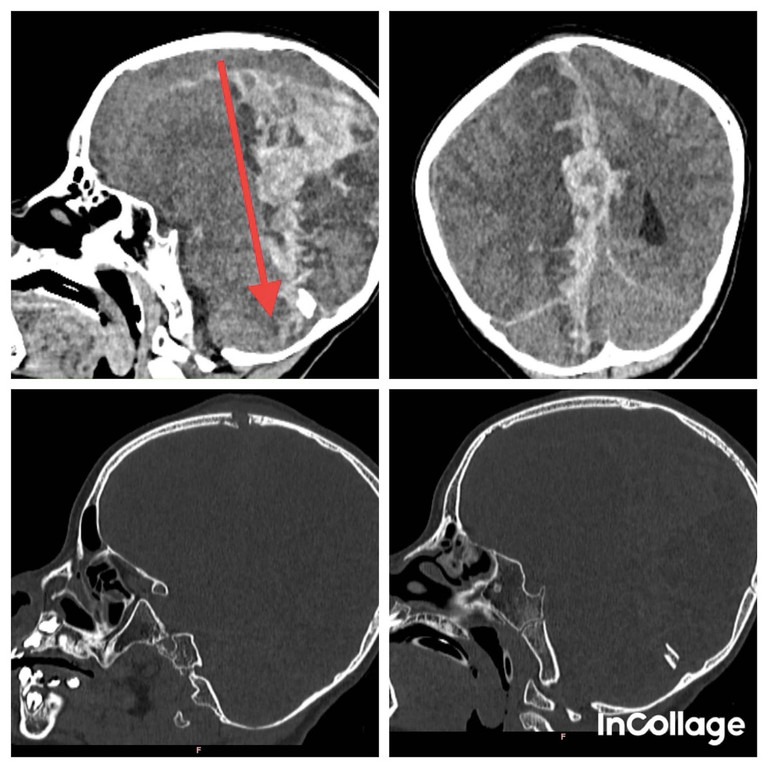

CT Scan ghi nhận tổn thương xuyên thấu qua não, từ phía trước đỉnh đầu đến phần tiểu não phía sau, gây xuất huyết não nhiều, chèn ép và phù não. Các bác sĩ phẫu thuật khẩn cấp để lấy máu tụ và mở sọ giải áp.

Thạc sĩ, bác sĩ Nguyễn Ngọc Pi Doanh, Khoa Ngoại Thần kinh, Bệnh viện Nhi đồng 2 cho biết vết thương gây ra do một lực cực kỳ mạnh, xuyên thấu và tổn thương nhu mô não. Sau 10 ngày phẫu thuật cấp cứu và tích cực điều trị, bé đang dần hồi phục, mở mắt, cử động tay chân tự nhiên. Hiện, trẻ đã được chuyển về Khoa Ngoại Thần kinh để tiếp tục theo dõi.

"Bé có dấu hiệu phục hồi tốt nhưng chắc chắn sẽ có di chứng về thần kinh do não đã tổn thương nặng, bé chưa nói được và còn yếu nửa người trái", bác sĩ Doanh nói, thêm rằng đây là tai nạn sinh hoạt hy hữu nhưng vô cùng nguy hiểm.